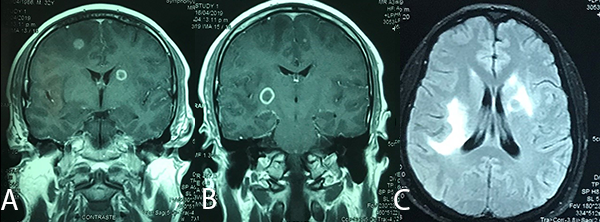

Imagen 1: RMN de cerebro: (A) y (B): cortes coronales en secuencia T1 con contraste donde se observan imágenes múltiples con captación de contraste en anillo. (C): corte axial en secuencia Flair que muestra edema peri lesional.

Las imágenes iniciales del paciente mostraron lesiones difusas. La secuencia T1 con contraste de la RMN mostró múltiples tuberculomas supra e infra tentoriales con un anillo que realza el contraste. Además en la secuencia Flair se evidenció edema perilesional de los tuberculomas. Sanei et al.(9) refieren que imagenológicamente la TBC en el SNC puede simular diferentes afecciones neurológicas (infecciosas y no infecciosas).